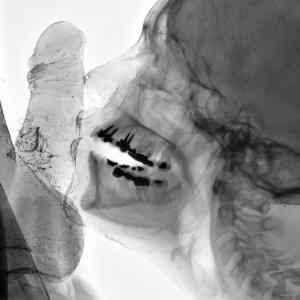

az na to ze tohle nejsou implantaty ale korenovy cepy ktery stoji zlomek ceny implantatu...

Kdyz vidis kvalitu chrupu tak ti musi byt jasny, ze jde o nejakou modelku nebo nekoho jinyho kdo ma zatracene hodne penez na implantaty ktery stoji vic nez si muze bezny clovek dovolit.

Podle zubů jeden pozná ledacos že? :-D

Obrazek zajimavy, ale kdyz vidim tu kvalitu chrupu...lepsi si nepredstavovat zbytek :-D